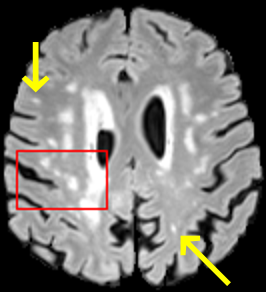

To test the impact of the iterative refinement on YODA’s translation quality, we compared regression and diffusion sampling on the RS data and present additional generation examples in Fig. 6. We observe that diffusion sampling visually resembles the appearance of the acquired images. Regression sampling preserves key anatomical features – the GM/WM boundary, WMHs (Fig. 4), the outline of the pallidum (Fig. 6) – but omits many high-frequency features. To investigate whether iterative refinement during diffusion sampling adds relevant and systematic medical information or only imitates acquisition noise, we performed ExpA sampling, i.e. averaging the output of several ( or ) diffusion trajectories. We observed a gradual loss of high-frequency details when increasing the (see also the supplementary video), indicating that the effect of the iterative refinement is non-systematic. For , the images are visually almost indistinguishable from the initial regression solution (see the supplementary video, and Fig.4 and 6). We directly compared the synthesis results of ExpA () and regression sampling quantitatively and found the differences to be minimal (SSIM: 99.73%, PSNR: 45.30 dB), i.e. diffusion sampling approaches the initial regression solution for a high . The quantitative analysis of the image quality (Tab. 1) showed that diffusion sampling impairs the assessed SSIM and PSNR in comparison to regression sampling for both the in- and external test sets, which we attribute to noise generation (Sec. 3.1). In turn, ExpA averages improved both metrics and, for , performed mostly on par with the regression solution in both test sets in terms of SSIM, while the PSNR in the RS was slightly increased (Tab. 1). However, we observed that ExpA sampling YODA improves the replication of systematic 3D low-frequency image intensity drifts (bias fields) due to the 3D synchronization in 2.5D diffusion sampling. Yet, this apparent advantage did not generalize to the external MBB dataset, as bias fields are MR protocol-specific.

For BraTS and IXI datasets, we noted the same convergence of visual appearance for diffusion to regression sampling when increasing the (Fig. 4) as observed in the RS. Also, we observed similar tendencies in terms of SSIM and PSNR, and for the performance of the respective downstream tasks (Tab. 2).

When analyzing the RS synthesis results (Fig. 4), we noted that most reference methods strive to imitate realistic images, but several artifacts can be observed such as hallucinated WMHs (SynDiff) and salt-and-pepper noise (SynDiff, I2I-Mamba, ResViT).

However, SelfRDB [29], and, especially, MADM [35] and the DB of Choo et al. [31] generate very smooth images (Fig. 4) with an high FID, i.e. low perceptual realism.

We attributes this to their self-consistent sampling procedures [29, 31] and/or accelerated DM sampling with entailed ExpA-like averages during the backward process [31, 35].